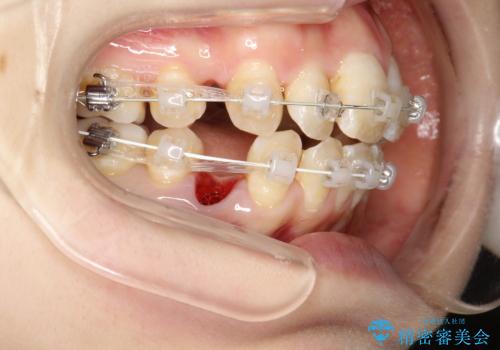

重度のガタガタ ワイヤーによる抜歯矯正

- 出っ歯と全体的ながたつきを主訴に来院されました。

上下の歯に重度のガタガタがあり、前歯が下の歯と咬んでいない状態でした。

審美装置を用いた、抜歯矯正を行うこととしました。

抜歯したスペースを使うことで、ガタガタと出っ歯を改善することができました。